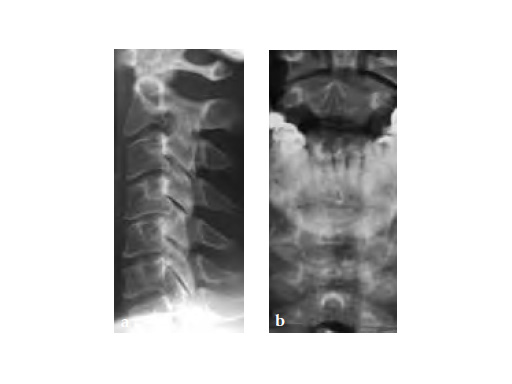

Case provided by Frank Kandziora, Frankfurt, Germany

59-year-old female with neck pain and right radicular arm pain C5 and C6 and weakness during walking. An MRI was performed and a severe DDD with soft spinal stenosis C3C6 was diagnosed. Neurophysiology revealed myelopathic spinal cord changes. Decompression and stabilization C3/4, C4/5, and C5/6 using Zero-P was performed. After surgery the patient was nearly free of pain, had no complains regarding dysphagia, and was neurologically improved.